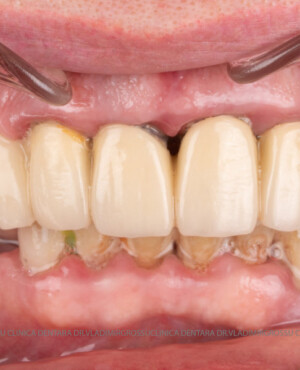

Caz 1